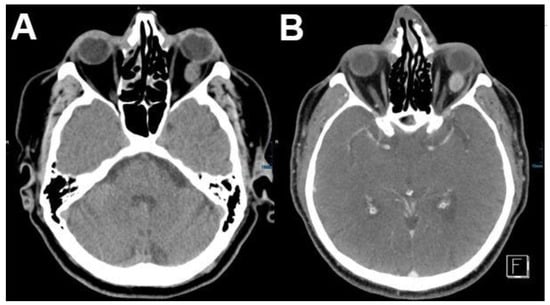

3.1.1. Retinoblastoma